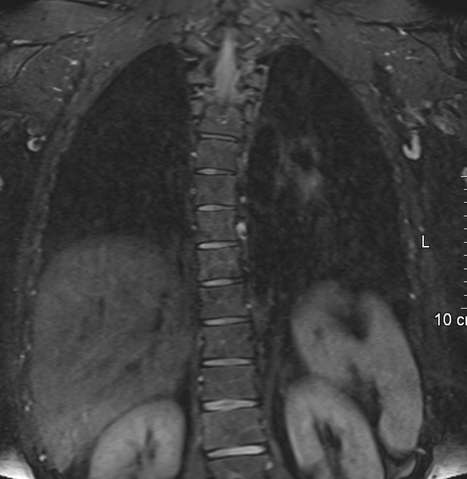

MRT der Leber mit Pfortaderastverschluss;. MRT der Leber mit Nachweis eines Herdes;. MRT der Leber dauert etwa 30 Minuten In einigen Fällen dauert das Verfahren viel länger, und die ganze Zeit müssen Sie bewegungslos bleiben Die Erfahrung ist nicht notwendig, wird das Gerät mit Innenbeleuchtung und Luftzufuhrsystem ausgestattet Der Patient ist in völligen Sicherheit MRT mit Kontrast.

MRT der Leber Die Magnetresonanztomographie, oder auch Kernspintomographie, ist ein strahlenarmes Untersuchungsmedium, welches eine gute Auflösung für Schichtbildaufnahmen von Weichteilstrukturen bringt Auch im MRT kann, wie im CT, zur Diagnosesicherung ein Kontrastmittel eingesetzt werden Das Hämangiom reichert sich mit dem Kontrastmittel. MRT der Leber Die Magnetresonanztomographie, oder auch Kernspintomographie, ist ein strahlenarmes Untersuchungsmedium, welches eine gute Auflösung für Schichtbildaufnahmen von Weichteilstrukturen bringt Auch im MRT kann, wie im CT, zur Diagnosesicherung ein Kontrastmittel eingesetzt werden Das Hämangiom reichert sich mit dem Kontrastmittel. Lebermetastase Variable Echostruktur, oft echoarm, multipel Arterielle Phase keine Anreicherung (außer Metastasen hypervaskulärer Tumoren) Portale Phase hypodens zur Umgebung Eventuell Dichte peripher höher als zentral („TargetLäsion“) T1w hypointens T2w hyperintens MehrphasenMRT nach KM wie CT Peripheres „washout“ in der.

Indikation Ein MRT der Leber wird immer dann durchgeführt, wenn andere bildgebende Verfahren keine genaue Darstellung der Leber gewährleisten können Im Allgemeinen kann man sagen, dass die Darstellung von Weichteilen und Nerven, Sehnen etc mit dem MRT besser darstellbar sind als zB in der Computertomographie Ein Röntgenbild hat bei der Darstellung der Leber keinen Sinn, da. Bei MRTUntersuchungen können ohne Strahlenbelastung und im Schichtverfahren völlig schmerzlos dreidimensionale Bilder erstellt werden MRT ist nicht zu verwechseln mit dem „Röntgen“ oder der Computertomographie Während bei diesen Verfahren Röntgenstrahlung zur Bilderstellung verwendet wird, basiert die Kernspinuntersuchung auf. MRT Leberdiagnostik mit dem leberspezifischen Kontrastmittel Gd EOB DTPA Dissertation zum Erwerb des Doktorgrades der Medi zin Fibrosierung der Leber nach Parenchymuntergang und regeneratorischem Parenchymumbau, wobei anschliessend die Wiederherstellung der normalen Leberarchite ktur nicht mehr möglich.